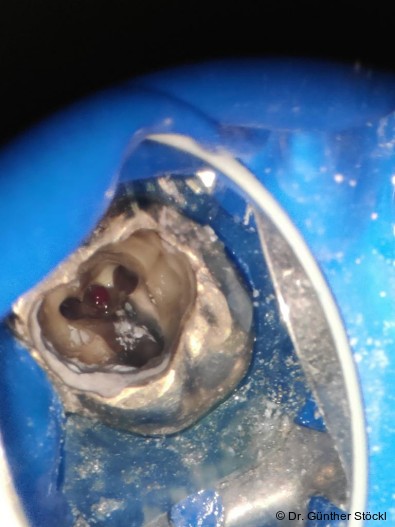

Foto: Dr. Günther Stöckl

Die Funktion des Wurzelkanalsealers besteht darin, die Hohlräume zwischen dem Kernfüllmaterial und den Dentinwänden zu füllen und eine dichte Verbindung herzustellen.14 Insbesondere die Penetration des Sealers in die Dentin­tubuli und anatomische Komplexitäten des Kanalsystems ist für eine suffiziente Versiegelung von entscheidender Bedeutung. Zu den Anforderungen zählen eine exzellente Versiegelungsfähigkeit, dimensionale Stabilität, Biokompatibilität, Unlöslichkeit gegenüber Gewebsflüssigkeiten, eine gute Adhäsion an den Kanalwänden sowie eine adäquate Verarbeitungszeit und einfache Handhabung.9, 10

Die fundamentalen Eigenschaften biokeramischer Materialien sind in ihrer chemischen Zusammensetzung und der ­daraus resultierenden Abbindereaktion verankert. Moderne Formulierungen basieren vorwiegend auf Kalziumsilikaten wie Trikalzium- und Dikalziumsilikat, häufig ergänzt durch Kalzium­alu­mi­nat, Kalziumoxid und Kalziumphosphat.1, 17 Eine wesentliche Weiterentwicklung gegenüber dem ursprüng­lichen MTA ist der Ersatz von Bismutoxid als Röntgen­kontrast­mittel durch Zirkoniumoxid oder Tantaloxid, wodurch das ­Risiko von Zahnverfärbungen, eine signifikante Einschränkung früherer Kalziumsilikatzemente, minimiert wird.17 Als hydrau­lische Kalziumsilikatzemente (HCSCs) benötigen diese Mate­rialien für ihre Aushärtung die Anwesenheit von Feuchtigkeit, was im endodontischen Milieu von erheb­lichem Vorteil ist.12 Bei Kontakt mit Gewebsflüssigkeiten oder der im Dentin vorhandenen Feuchtigkeit wird eine Hydrata­tions­reak­tion initiiert. Dieser Prozess führt zur Bildung eines Kalzium­silikat­hydrat-­Gels sowie zur Freisetzung von Kalzium­ionen (Ca2+) und Hydroxid­ionen (OH−), was zur Entstehung von Kalzium­hydroxid als Nebenprodukt führt. Dieser zen­trale Mechanismus bildet die Grundlage für nahezu alle weiteren physikalischen und biologischen Eigenschaften des Materials.9, 17 Die physikalisch-chemischen Eigen­schaften sind für die klinische Handhabung und die Langzeitstabilität der endodontischen Versorgung von entscheidender Bedeutung.

Die Partikelgröße des Zements beeinflusst die Abbindekinetik maß­geblich; kleinere Partikel vergrößern die reaktive Oberfläche, was die Hydratation beschleunigt und die Abbindezeit verkürzt. Gleichzeitig verbessert eine feine Par­tikel­vertei­lung die Penetration des Sealers in mikroanatomische Strukturen wie die Dentin­tubuli, was für einen hermetischen Verschluss essenziell ist. Studien belegen, dass biokeramische Sealer (z. B. Komet BioSeal) eine signifikant tiefere Penetration in die Dentin­tubuli erreichen als der Goldstandard AH Plus.17 Moderne, vorangemischte Formulierungen bieten zudem gegenüber MTA eine deutlich verkürzte Abbindezeit und eine erheblich vereinfachte Handhabung, was die klinische Effizienz und Standardisierung verbessert.17, 1 Ein idealer Sealer sollte unlöslich in Gewebsflüssigkeiten sein, um die Integrität des apikalen Verschlusses dauerhaft zu sichern.9 Einige Studien berichten für bestimmte vorangemischte Biokeramiken über eine höhere initiale Löslichkeit im Vergleich zu den ISO-­Normen oder zu AH Plus.